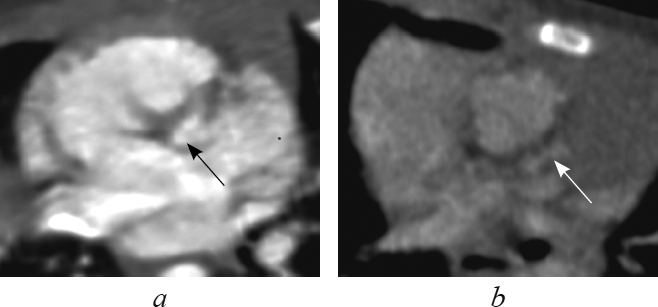

Анатомические признаки ушка, характерного для морфологически правого предсердия (треугольная форма с тупой вершиной, широкое соединение с предсердной полостью, слабо выраженная дольчатость [1, 2, 4, 16]), определяют в реформации по длинной оси приносящего тракта правого желудочка (рис. 1). В этой реформации видно, что при транспозиции морфологически правое предсердие соединяется с морфологически правым желудочком (см. рис. 1, а), а при корригированной транспозиции морфологически правое предсердие — с морфологически левым желудочком (см. рис. 1, b).

Рис. 1. В реформации по длинной оси приносящего тракта правого желудочка ушко морфологически правого предсердия при транспозиции магистральных сосудов (а, стрелка), при корригированной транспозиции магистральных сосудов (b, стрелка)

Fig. 1. Long-axis of right ventricle inflow tract reformation. The eyelet of the morphologically right ventricle in great arteries transposition (a, arrow) and in corrected great arteries transposition (b, arrow)

Анатомические признаки ушка, характерного для морфологически левого предсердия (узкая вытянутая форма с заостренным концом, узкое соединение с предсердной полостью, хорошо выраженная дольчатость [1, 2, 4, 16]), определяют в реформации левых камер сердца (рис. 2). В этой реформации обращает на себя внимание соединение морфологически левого предсердия с морфологически левым желудочком при транспозиции (рис. 2, а), соединение морфологически левого предсердия с морфологически правым желудочком при корригированной транспозиции (рис. 2, b).

Рис. 2. В реформации левых камер сердца ушко морфологически левого предсердия при транспозиции магистральных сосудов (а, стрелка), при корригированной транспозиции магистральных сосудов (b, стрелка)

Fig. 2. Left heart chambers reformation. The eyelet of the morphologically left ventricle in great arteries transposition (a, arrow) and in corrected great arteries transposition (b, arrow)